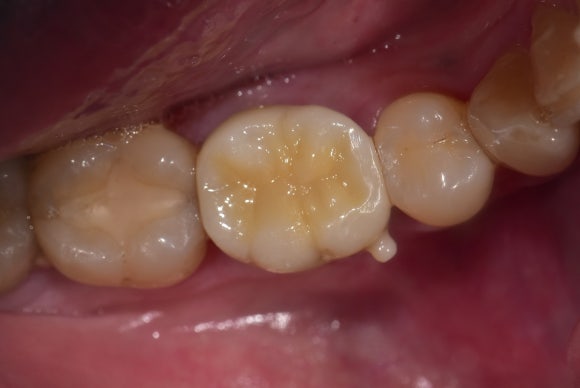

20250627

마지막으로 이렇게,

튼튼한 크라운을 씌워서 치료를 종료합니다.

하방에 뿌리가 없는 부위는

씹는 힘이 약하게 전달되도록 조정합니다.

과한 힘을 받으면,

새로 만든 크라운이나

남아있는 뿌리에 손상이 생길 수 있기 때문입니다.

이러한 역학적 불리함 때문에

온전한 자연치에 크라운을 씌운 것이나

임플란트를 한 것에 비해서는

오래 쓰지 못할 수 있습니다.

하지만 건강상의 이유 (골다공증, 출혈성향, 항암 등)로 당장 발치를 하지 못하거나,

자연치에게 마지막 기회를 주고 싶은 분들께는

충분히 권장되는 시술입니다.